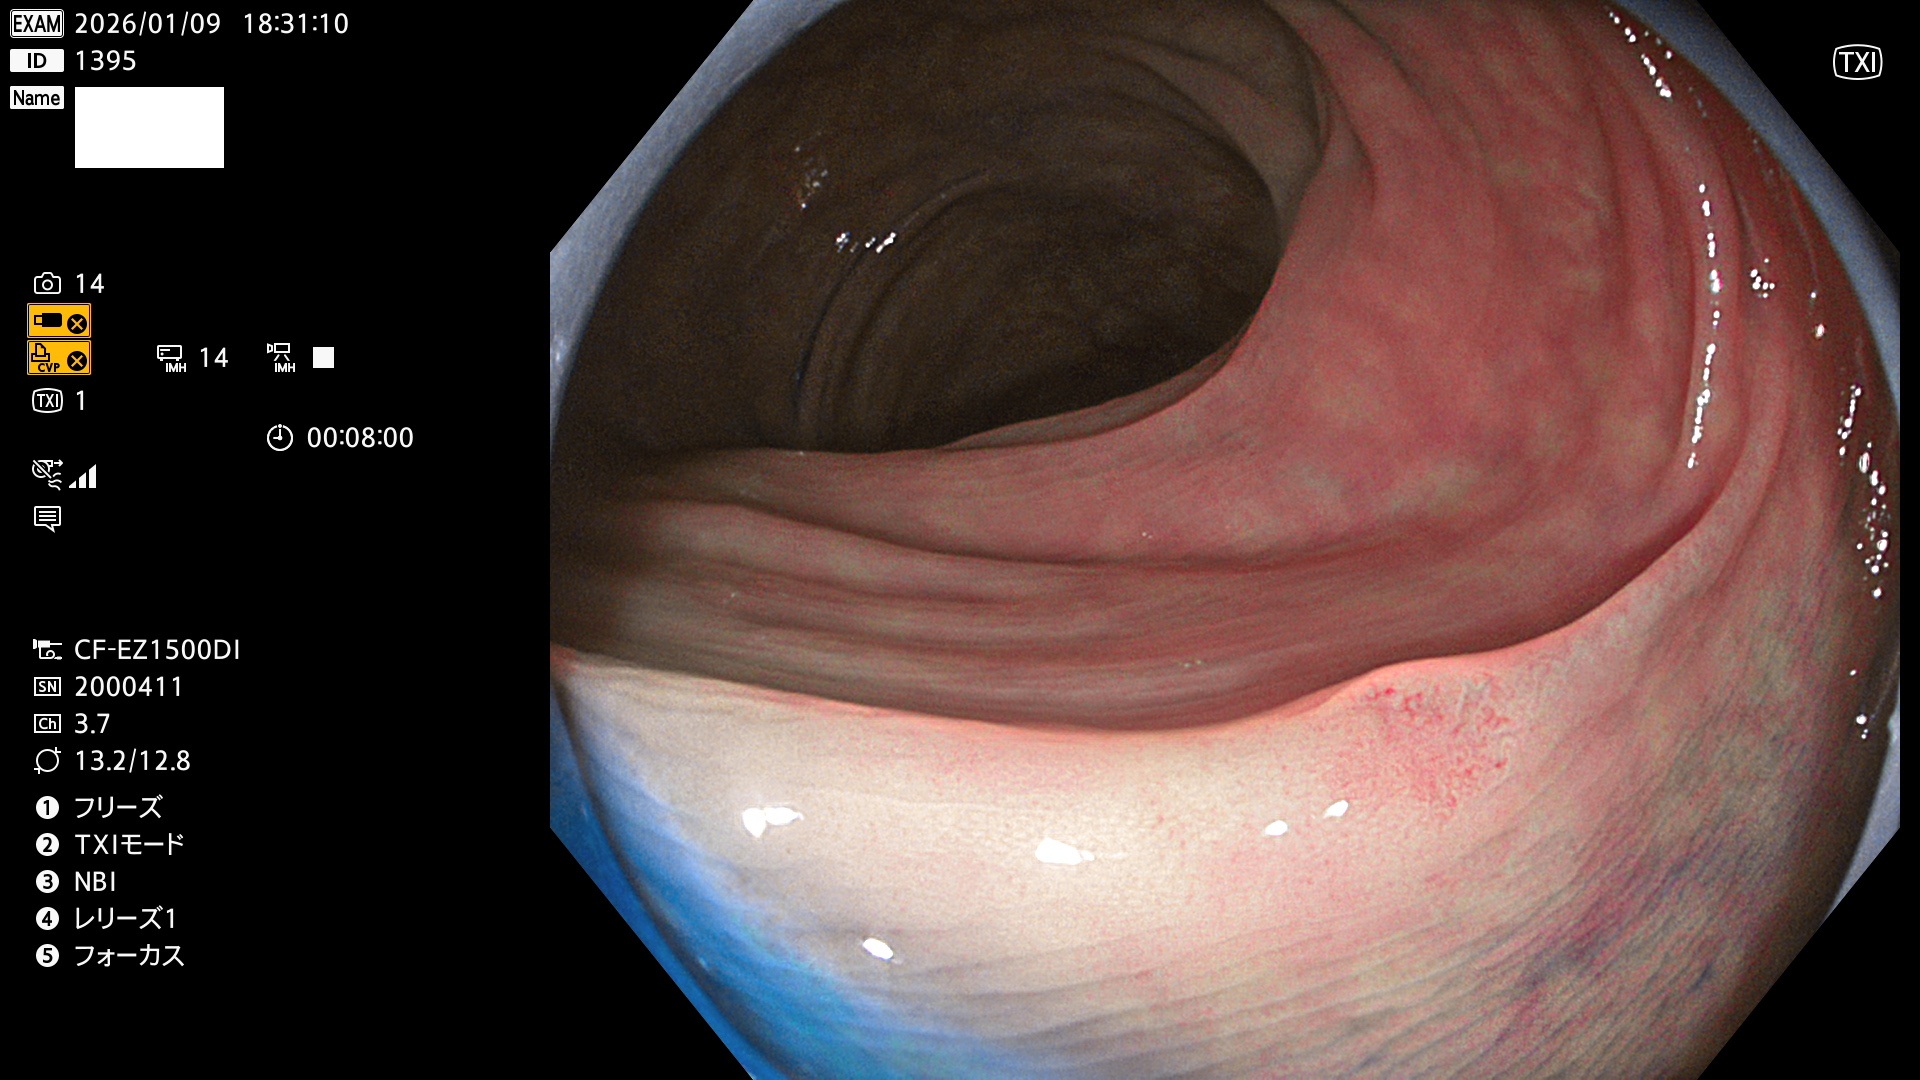

完全に平坦な物をUb、陥凹している物をUcと呼びます。Ubは認識が困難で、Ucはびらん(炎症)と紛らわしいために見落とされやすく、「内視鏡後・大腸癌」の原因になります。

専門的)Uc=De Novo癌? 内視鏡の解像度が低かった時代、このような説もありました。しかし今日の高精度内視鏡では良性の微小なUc型腺腫(APC遺伝子異常の腺腫)が日常的に見つかります。Ucこそが多段階発癌(Adenoma-Carcinoma Sequence)のMain Routeです。

毎週の検査(木・金・土・日)に発見されたUbとUc型・腺腫を、その週の日曜の夜にUPし1週間、提示します。

2026年1月8日〜1月11日の4日間(40件)6個 (Uc_ADR=6個/40人=15%)